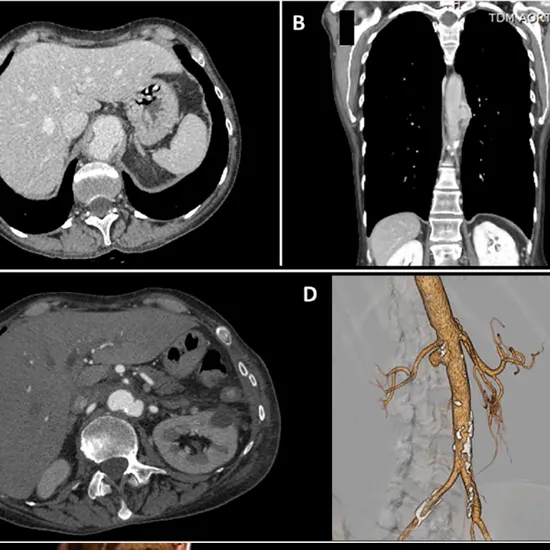

CT Aortic Angiography is a diagnostic imaging procedure used to assess the flow of blood through the aorta. The aorta is the major artery responsible for transporting blood from the heart to the abdomen. This scan aids in assessing the blood supply to the upper body and detecting/diagnosing aortic and aortic branch diseases such as atherosclerosis. Contrast dye will be injected into the arteries during the procedure, and x-rays will be used to detect any potential aortic problems.

Its clinicians use dye injected into the bloodstream to visualise artery blockages. The scan reveals a blockage when the dye reaches impenetrable or narrowed passages clogged by fatty build-ups or clots.

CT Aortic Angiography is used by doctors to diagnose issues with the aorta and its branches, such as aortic aneurysm, peripheral artery disease, aortic dissection, congenital problems, Double aortic arch, vascular ring, aortic blockages, and so on. It is also used to detect suspected aortic injuries and to diagnose aortic inflammatory conditions.